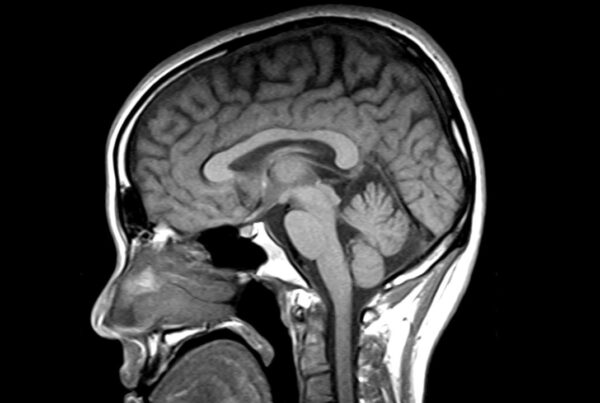

La resonancia magnética está revolucionando el diagnóstico de enfermedades neurológicas poco frecuentes que durante años se confundieron con el Parkinson o el envejecimiento.

Un estudio del IR Sant Pau, en Barcelona, demuestra que esta tecnología permite identificar con mayor precisión la parálisis supranuclear progresiva (PSP) y la degeneración corticobasal (CBD), dos trastornos infradiagnosticados.

La resonancia magnética permite detectar “firmas cerebrales” específicas:

- En PSP: daño en el tronco encefálico

- En CBD: afectación cortical relacionada con el movimiento

Además, ayuda a medir la progresión de la enfermedad y mejorar los ensayos clínicos, reduciendo hasta un 50 % los pacientes necesarios en PSP y hasta un 85 % en CBD. A futuro, combinar resonancia con análisis de sangre podría permitir diagnósticos aún más tempranos.